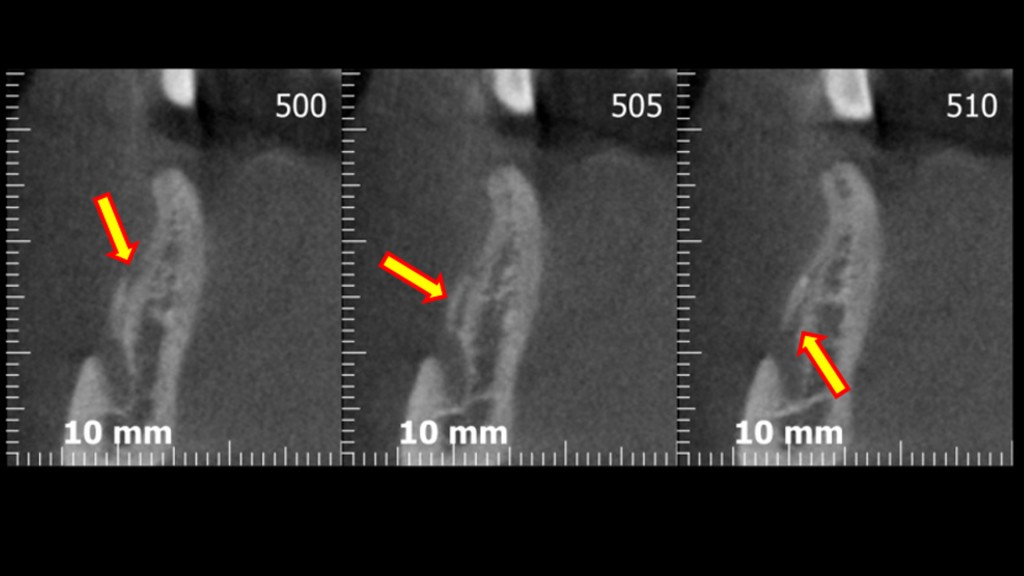

Avevi notato questo? Dai tagli della cone-beam si nota chiaramente una variante anatomica abbastanza importante: un foro mentoniero accessorio posizionato più o meno a metà tra la cresta e il foro primario, diciamo circa 7 mm apicalmente alla cresta, dal quale emerge un ramo di diametro rilevante del nervo alveolare inferiore. Chissà a quale parte del mento o del labbro porta le sensibilità quel piccolo ramo!? Diciamo che per mantenere immacolato il mio palmares medico legale preferisco non scoprirlo!

Infatti ben poco sotto il livello della cresta compare l’infame…